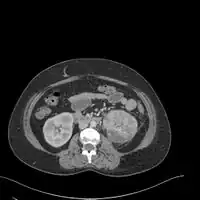

If a kidney stone is suspected (e.g. on the basis of characteristic colicky pain or the presence of a disproportionate amount of blood in the urine), a kidneys, ureters, and bladder x-ray (KUB film) may assist in identifying radioopaque stones.[9] Where available, a noncontrast helical CT scan with 5 millimeter sections is the diagnostic modality of choice in the radiographic evaluation of suspected nephrolithiasis.[17][18][19] All stones are detectable on CT scans except very rare stones composed of certain drug residues in the urine.[20] In patients with recurrent ascending urinary tract infections, it may be necessary to exclude an anatomical abnormality, such as vesicoureteral reflux or polycystic kidney disease. Investigations used in this setting include kidney ultrasonography or voiding cystourethrography.[9] CT scan or kidney ultrasonography is useful in the diagnosis of xanthogranulomatous pyelonephritis; serial imaging may be useful for differentiating this condition from kidney cancer.[10]

Xanthogranulomatous pyelonephritis is an unusual form of chronic pyelonephritis characterized by granulomatous abscess formation, severe kidney destruction, and a clinical picture that may resemble renal cell carcinoma and other inflammatory kidney parenchymal diseases. Most affected individuals present with recurrent fevers and urosepsis, anemia, and a painful kidney mass. Other common manifestations include kidney stones and loss of function of the affected kidney. Bacterial cultures of kidney tissue are almost always positive.[25] Microscopically, there are granulomas and lipid-laden macrophages (hence the term xantho-, which means yellow in ancient Greek). It is found in roughly 20% of specimens from surgically managed cases of pyelonephritis.[10]